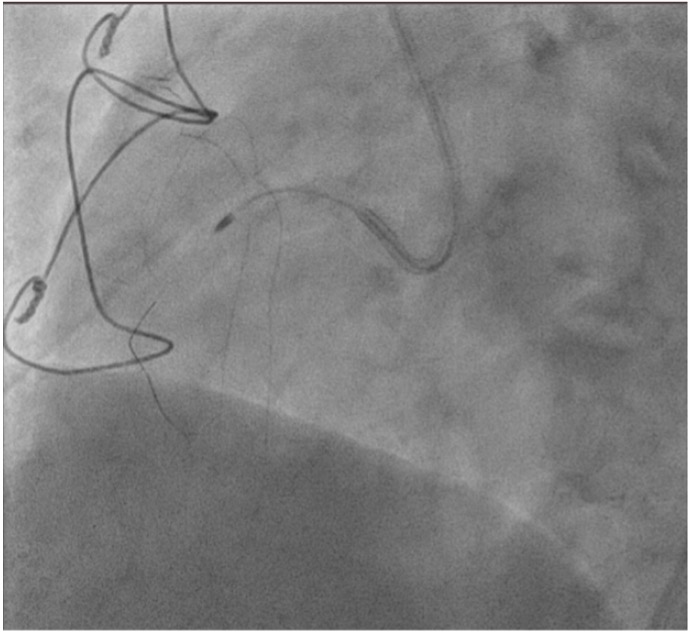

Right femoral arterial access was taken with 7F long sheath (45cm) and RCA was engaged with 7F AL 3.5 catheter. We failed to cross proximal lesion with Rinato wire (Asahi Intecc, Japan) but crossed with Fielder XT-R (Asahi Intecc, Japan). We had difficulty in crossing the distal lesion due to inadequate guide support and inability to deliver microcatheter beyond proximal calcific lesion. Proximal lesion was predilated with 2.5 mm NC balloon but the balloon got ruptured. Fielder XTR wire was exchanged with Rota floppy wire (Boston scientific, Japan) with corsair microcatheter (Asahi Intecc, Japan) delivered just beyond proximal lesion. Temporary pacemaker inserted and Rotablation of the proximal RCA lesion was done with 1.5 mm Rota burr. Post proximal lesion modification corsair could be delivered to Distal lesion, and lesion crossed with Ultimate Bros 3 (Asahi Intecc, Japan) followed by de-escalation to Fielder XT-R wire. The proximal lesion was then dilated with 3.5x10mm Wolverine Cutting balloon (Boston Scientific, Ireland) to deliver a 7F Guideliner beyond the proximal lesion for better support to further gear advancement. As 1mm balloon stuck within the distal lesion, grenadoplasty was performed followed by an exchange to rota wire with corsair. Rotablation of distal RCA lesion was done with 1.5 mm burr through guide extension. Further dilatation of distal lesion was done with 3mm IVL balloon followed by stenting with 3.25 x 28 mm drug-eluting stent with good TIMI 111 flow.